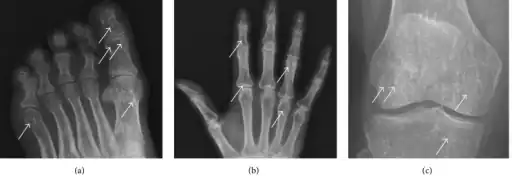

a-c)Osteopoikilosis in feet, hand, knee

In terms of the diagnosis Osteopoikilosis is radiographically evaluated via the presence of multiple symmetrical circular sclerotic opacities [2]

The radiographic appearance of osteopoikilosis on an X-ray is characterized by a pattern of numerous white densities of similar size spread throughout all the bones. This is a systemic condition. It must be differentiated from blastic metastasis, which can also present radiographically as white densities interspersed throughout bone. Blastic metastasis tends to present with larger and more irregular densities in less of a uniform pattern. Another differentiating factor is age, with blastic metastasis mostly affecting older people, and osteopoikilosis being found in people 20 years of age and younger.

The distribution is variable, though it does not tend to affect the ribs, spine, or skull.[3]